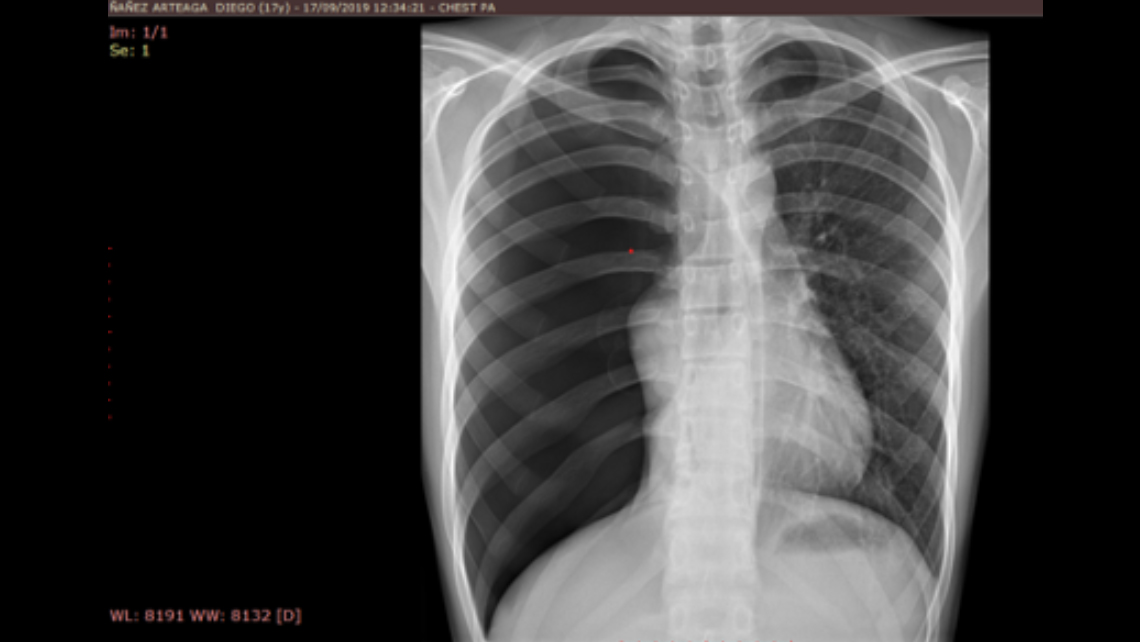

Se trata de paciente masculino de 17 años, quien refiere dolor torácico súbito y disnea, sin antecedentes traumático, sin antecedentes previos, se procede a realizar estudio radiológico de tórax.

Se evidencia todo el hemitorax derecho con incremento de la radiotransparencia, asimétrico con respecto al hemitorax izquierdo, observándose a nivel hiliar derecho áreas sugestiva de parénquima colapsado, además se observa leve desplazamiento del cardiomediastino a la izquierdo, el parénquima del hemitorax izquierdo es normal. DICHOS HALLAZGOS SON COMPATIBLES CON NEUMOTÓRAX DERECHO MASIVO ESPONTANEO. Se deriva para completar sus estudios de tomografía y evaluación por especialidad correspondiente.